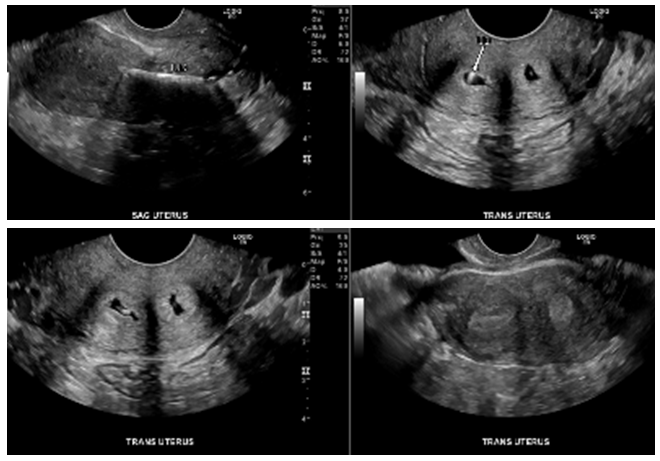

A 15-year-old Hispanic female, G0P0, initially presented with persistent sharp right lower quadrant pain. The patient was treated for pelvic inflammatory disease but, during further evaluation to rule out ovarian cyst and ovarian torsion, the patient was discovered to have severe primary dysmenorrhea, MDA and a solitary kidney. Ultrasound (Figure 1) and magnetic resonance imaging (MRI) (Figure 2) revealed a uterus didelphys with obstructed Hemivagina and Ipsilateral renal agenesis (OHVIRA syndrome) also known as Herlyn-Werner-Wunderlich Syndrome (Figure 3). Ultrasound indicated a 7.1 x 7.0 x 7.2 cm thick-walled right adnexal structure containing debris and fluids, which represented uterine didelphys with hematometra of the right-sided uterine horn (Figure 1 & 2). There was also a left uterine horn, which was oriented in the left pelvis and appeared unremarkable. Initial reproductive endocrinology and infertility recommendation was for 6 months of Leuprolide (Lupron) followed by continuous oral contraceptives (OCP) (with no placebo week), which the patient completed. However, the patient started getting her menstrual period every month (heavy and painful) while on OCP. The OCP was stopped and once the bleeding stopped the patient was re-started on 6 months of Lupron with norethindrone add back therapy, followed by continuous OCP (with no placebo week). The patient is currently scheduled to discuss the surgical option of hemi hysterectomy of the right rudimentary uterus versus resection of vaginal septum to open of obstructed Hemivagina.10

Figure 1 Patient 1: Pelvic Ultrasound, Transverse View 10/26/16: A 7.1 x 7.0 x 7.2 cm thick-walled right adnexal structure containing debris and fluid, this represent uterine didelphys with hematometra of the right-sided uterine horn. There is also uterine horn, which is oriented in the left pelvis and appears unremarkable.

In all three cases pelvic ultrasound was initial imaging tool. The ultrasound in case 1 (Figure 1) and subsequent MRI (Figure 2) shows a lobular tubular thick wall cystic structure in the right pelvis suggesting hemorrhagic contents extending into the right aspect of the posterior vagina and didelphys uterus. MRI of the abdomen depicts renal agenesis, demonstrating abnormal kidney development confirming HWW. As per the classification presented by Zhu and imaging, the patient has a class 1.2 OHVIRA.2 The ultrasounds in cases 2 and 3 (Figures 6 & 9 respectively) both demonstrate didelphys uterus with two cervices. The additional MRI in case 2, revealed two separate cervices and two uteri one with a retained IUD. MDA can be associated with a vaginal septum, more commonly vertical (Case 2 & Figure 5) but cases of a horizontal septum have also been reported (Case 1 & Figure 8).14